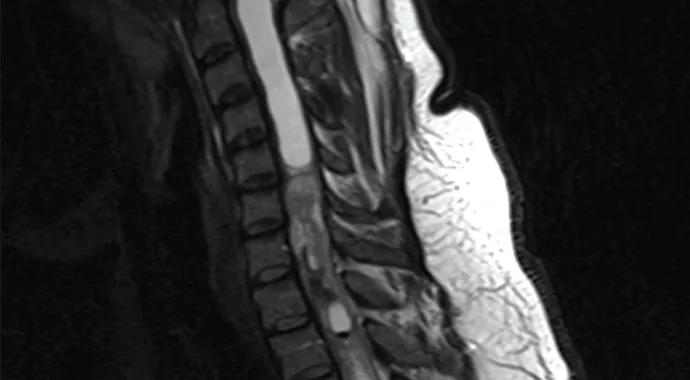

Sometimes life comes at our patients fast. Consider Kristen, a young lady who sought care at Cleveland Clinic’s Center for Spine Health a few years ago, when she was 28. Life was quite good for Kristen: She had married Nick in 2009, and they shared dreams of having a family and building a fulfilling life together. Her zest for life was palpable. Suddenly, however, her world began to collapse. First she had a miscarriage eight weeks into her first pregnancy. Then she had a skin lesion removed that proved to be malignant melanoma. Throughout all this, she was experiencing escalating neck pain, which she largely ignored because of all her other stressors. As the pain progressively worsened, she developed problems with balance and coordination. MRI of her spine revealed yet another problem — an intramedullary cervical spine tumor (i.e., within the substance of the spinal cord; Figure 1).

Figure 1.Spine MRIs showing the intramedullary cervical spine tumor.